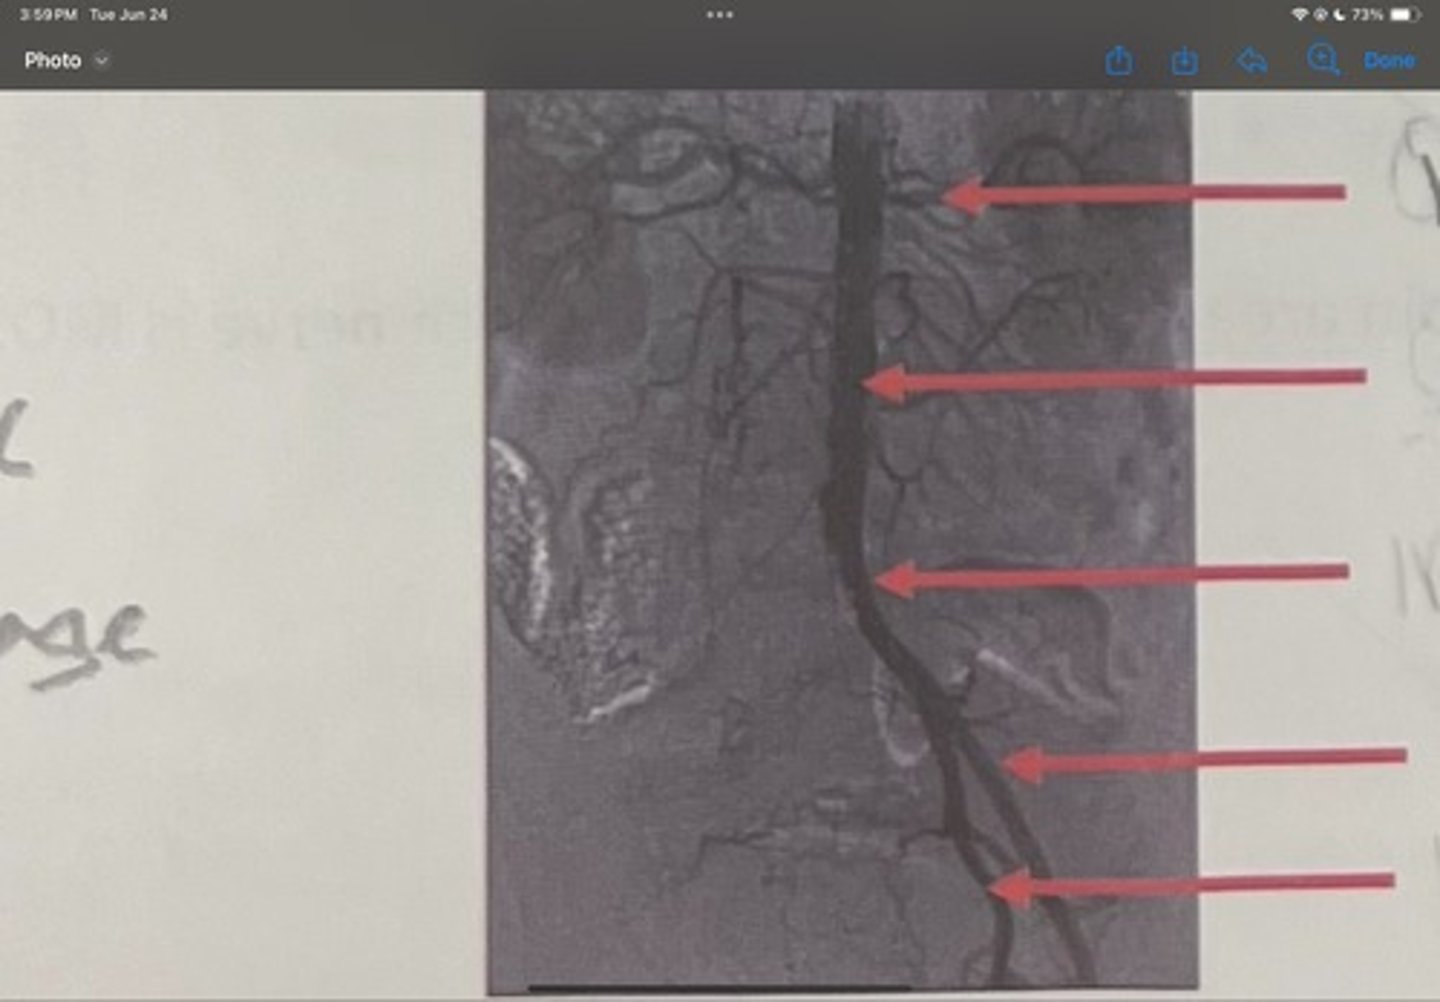

Renal artery

What is the 1st one

Abdominal aorta

What is the 2nd one

Common iliac artery

What is the 3rd one

External iliac artery

What is the 4th one

Internal iliac artery

What is the 5th one

right common iliac artery blockage

What is the pathology of the image